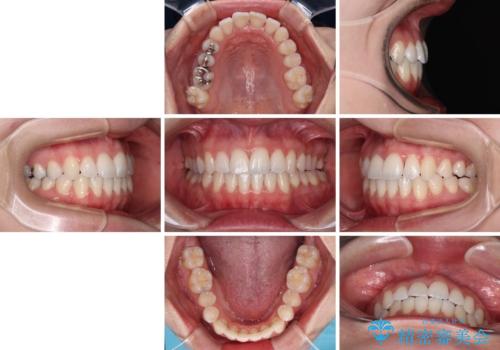

急速拡大装置により骨格はある程度改善されましたが、奥歯の咬み合わせ改善に非常に時間がかかってしまいました。

デコボコを改善させるだけでなく、しっかりとした咬合状態を獲得することができ、患者様には大変満足していただけました。